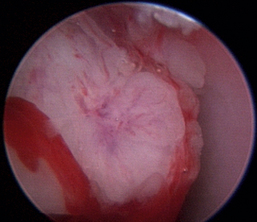

Normal turbinates have a smooth, pink-to-white surface and a spatial alignment that provides channels for the passage of air. The color varies and appears tan in the caudal nasal cavity. Turbinates come in different shapes and sizes, but the surface should be smooth. Ethmoid turbinates in the caudal nasal cavity will have a characteristic stippled or corrugated appearance (Figures 19-13 through 19-16). Ulcerations or various proliferations of the mucosa are indicative of disease. These changes are typically diffuse and accompanied by a lot of mucus. Mucus can be thin to purulent. Copious amounts can be flushed out of the nasal cavity to allow better visibility. The specific disease is determined by biopsy. After full examination of the nasal cavity, run the scope along the floor of the nasal sinus to the level of the choanae. Keeping the scope pointed in a ventral medial direction prevents inadvertent trauma or penetration of the cribriform plate. The index finger of the free hand can be used to follow the scope as it moves caudally over the hard palate; the surgeon can then palpate the scope through the soft palate when it moves into the nasopharynx. Some force is needed to complete this procedure and may result in increased bleeding.

Figure 19-15 Normal canine nasal turbinate mucosa.

image